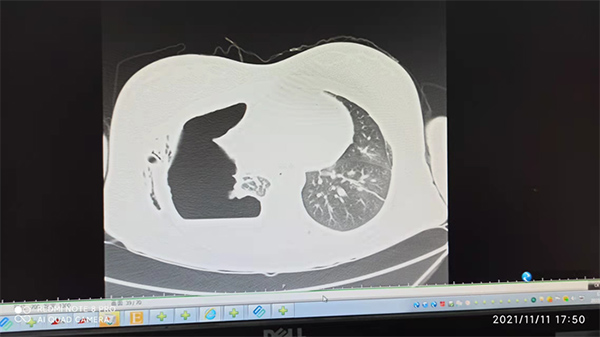

今年3月,患者查出右肺结节,同年5月出现咳嗽、咳痰、气短,7月复查胸部CT提示中等量气胸,发现右下叶背段残端瘘。支气管胸膜瘘是临床上较为严重且罕见的术后并发症之一,尤其是肺叶/全肺切除术后的支气管残端瘘,处理起来非常棘手。

9月26日,患者首次来到应急总医院,检查发现右下叶背段支气管手术残端瘘,给予镜下治疗后复查右侧气胸较前减小,右肺部分复张较前改善。本以为该患者的病情会由此好转,可是没想到的是,10月15日,患者突发咳嗽、咳大量黄痰,伴呼吸困难、右侧胸痛,复查发现右侧液气胸。10月18日,患者再次来到应急总医院治疗。

术前